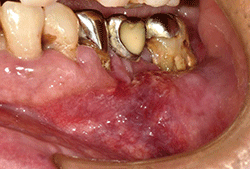

図❶ 初診時の口腔内写真

現症:下顎左側臼歯部頬側歯肉に、発赤を伴うび漫性の膨隆を認めた。舌側歯肉に膨隆は観察されなかった(図❶)。触診にて45相当頬側歯肉に軽度の硬結を触知し、⑤⑥⑦ブリッジの支台歯である57は3度の動揺(Millerの方法による)であった。また、下唇左側に知覚麻痺を認めた。頬部および頸部に異常所見はみられなかった。